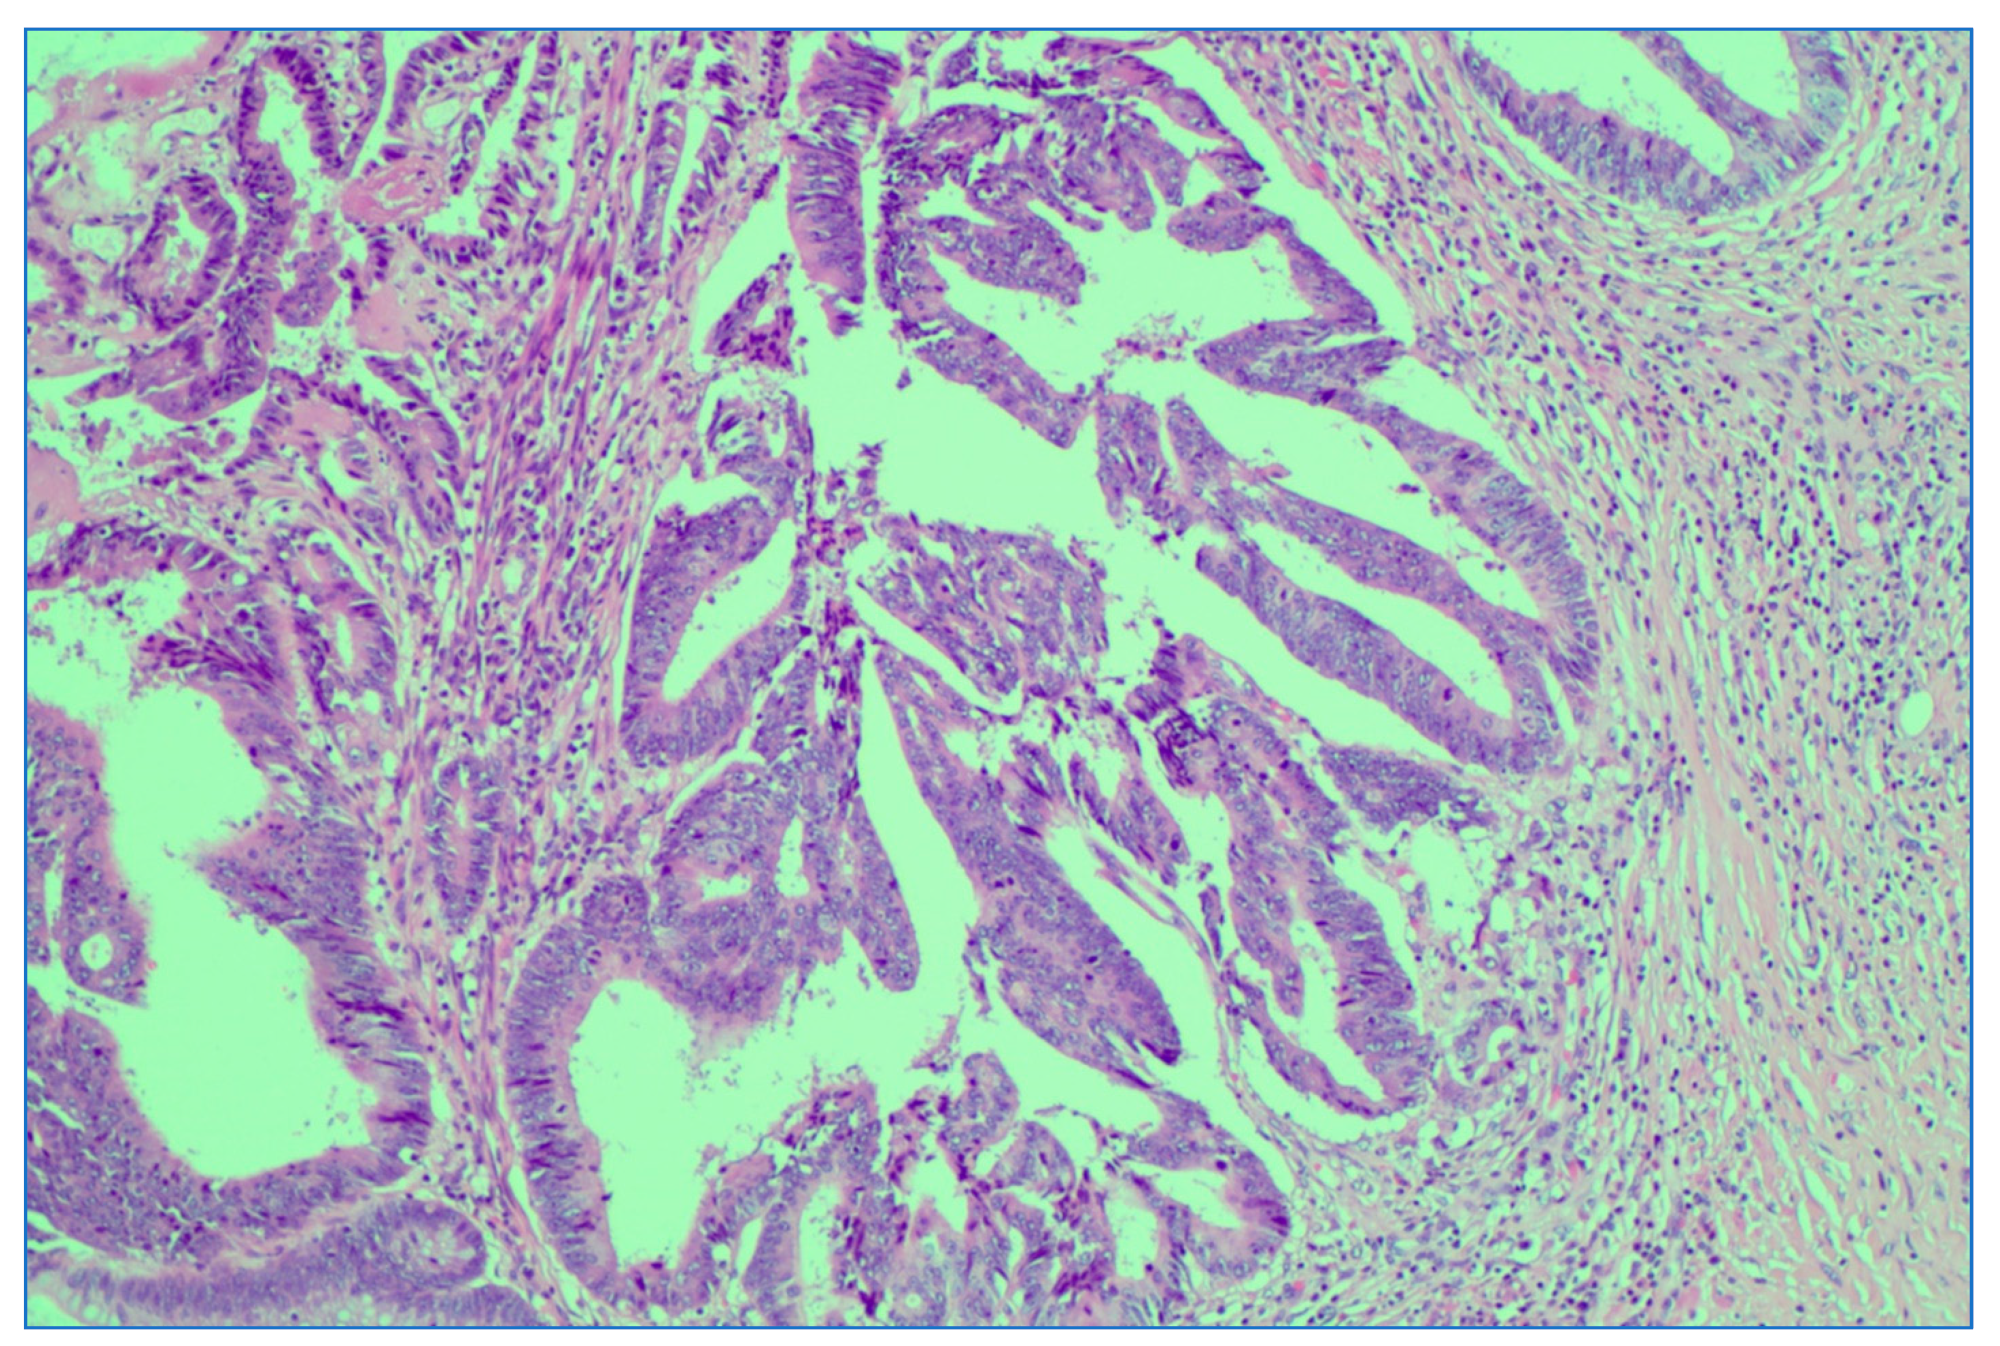

Figure 10.

Downstage of rectal adenocarcinoma after neoadjuvant LCRCT radiochemotherapy. Illustrated is a downstaged ypT1 with invasion in submucosa; HE stain × 10 magnification.